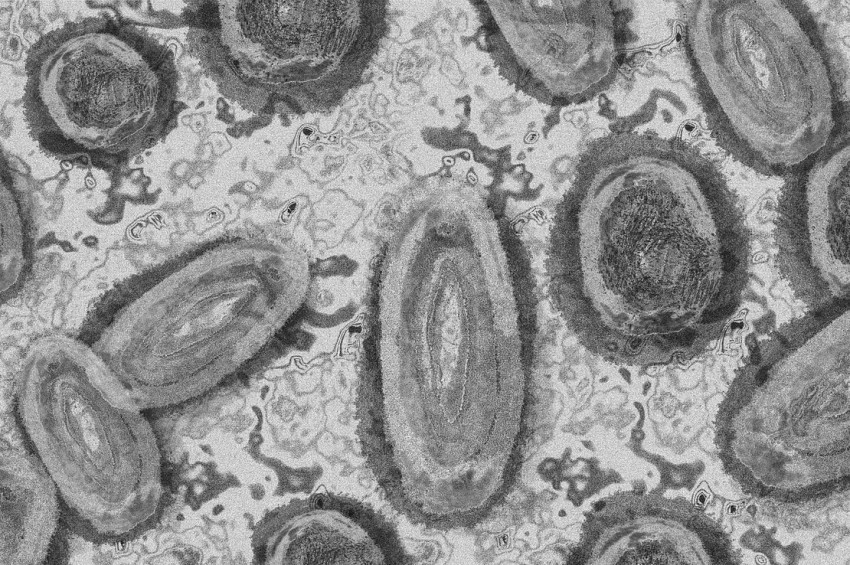

Maymun çiçeği virüsü belirtileri nelerdir?Maymun çiçeği virüsü nerede görüldü? Maymun çiçeği virüsü nasıl bulaşır? Belirtileri nelerdir?

Maymun Çiçeği Virüsü belirtileri alerjik döküntülerden nasıl ayrılabilirMaymun Çiçeği virüsünün nasıl bulaşır? Kuluçka süresi ne kadardır? Maymun Çiçeği Virüsü Hastalığının döküntülerin alerjik döküntülerden farklı olarak nerelerde yoğunlaşıyor?

Maymun Çiçeği Virüsüyle ilgili bilinmesi gereken 5 önemli noktaMaymun Çiçeği Virüsünün hızlı mutasyona uğrayarak insanlara bulaşması Covid-19 gibi kolay olmadığından pandemi beklentisi bulunmamaktadır